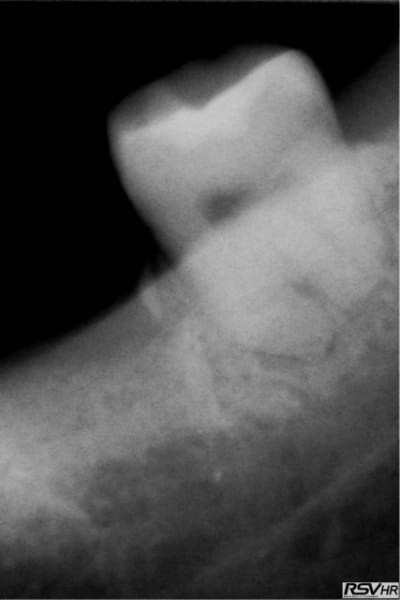

Pour Pluton

voici le cas extraction en décembre 2011 ce qui me pose problème c'est le 2eme implant le 8 mm passe mais le col ne serait pas enfoui , ne vaut il donc pas mieux plus enfouir un 6 mm d'où ma question.

L'os dans le 2 eme site est type 4 et type 3 vers le fond et avec le 8 mm je me retrouve dans la corticale linguale

sinon le deuxième site, moi, me paraît louche...c'est pas du D4, j'aurais plutôt tendance à dire que c'est du tissu de granulation...( et peut être bien un petit morceau de racine...c'est pas très net...)

une racine le morceau en distal e je l'ai enleve avant le scan, la radio date du 21.1 et le scan du 14.3.... je ne pense pas avoir de pano d'ensemble post extractionnel.

oui, donc tu es à 8 semaines post extraction pour ton scan...c'est un peu juste pour juger de la densité osseuse, non?

au mieux tu es dans de l'ostéoïde...sinon dans du TG...

et non pas à 8 semaines je l'ai extraite le 19.11.2011 donc c'est plus et je te joins une retro avant l'extraction la dent ne présentais pas de lésion paro enorme donc je ne vois pas pourquoi un TG se serait développé plus facilement.

Lev3 a36qqm - Eugenol

c'est pas parce que t'as mis des éponges que tu n'as pas eu une petite alvéolite qui a retardé la cicat (chose fréquente quand on utilise une fraise pour faire une alvéolectomie/séparation...)

à 4 mois amha çà devrait être plus dense si tout était normal...

a mon avis, sur la 2eme zone d'implant, t'es dans de la soupe! tu vas au casse-pipe si tu plantes...(j'ai déjà eu ce genre d'image et conclusion...)

la lacune semble bien délimitée par des parois, donc tu peux tenter: ouverture curetage et comblement.